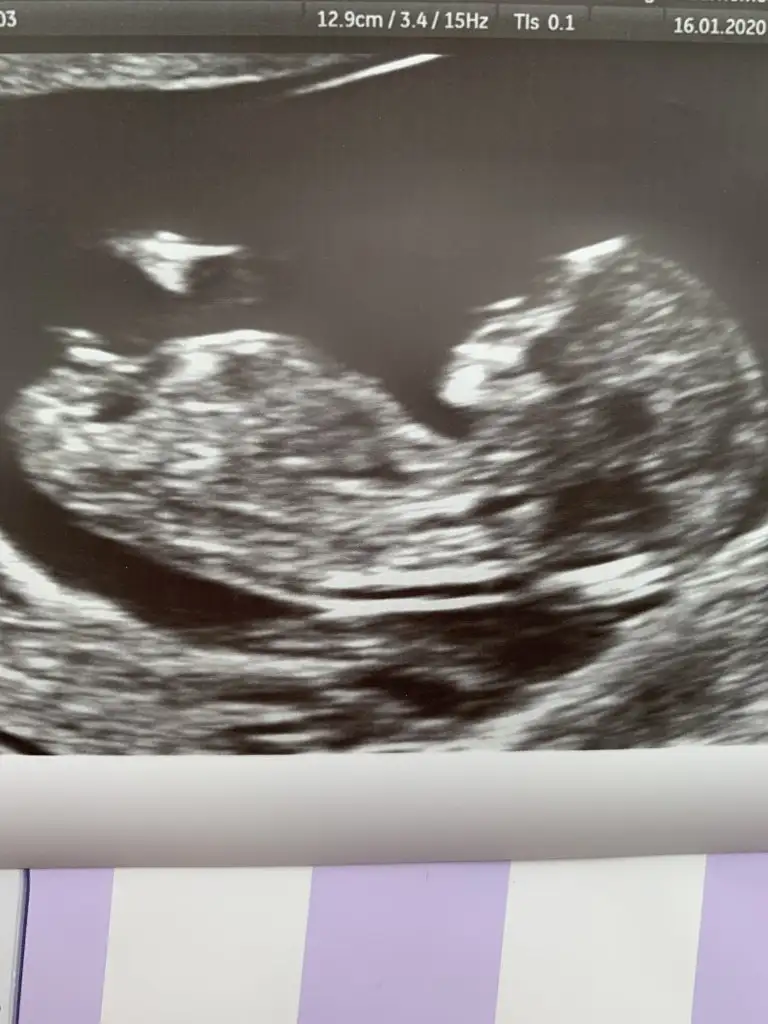

Arada kaldım yüzde altmış kız yüzde kırk erkek

Teşekkür ederim. Hayırlısı sağlıklı olsun inşallah. Doktora da sordum da bakti epey hic fikir yürütemiyorum dedi hangi resme göre yorumladınız birinde sırtı dönük gibi. Yanılıyor muyum?Arada kaldım yüzde altmış kız yüzde kırk erkek